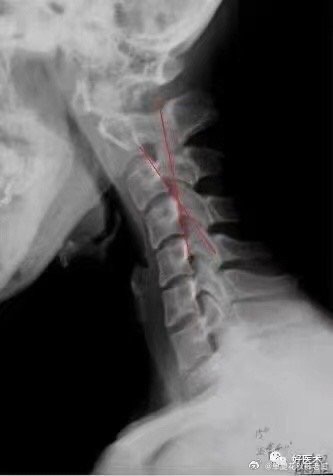

颈椎病不一定都是脖子疼

脑梗塞、眩晕、肩周炎、甲状腺疾病、哮喘、咽喉问题及咳嗽,手指、手臂麻木酸疼,心血管病等颈椎问题值得大家关注